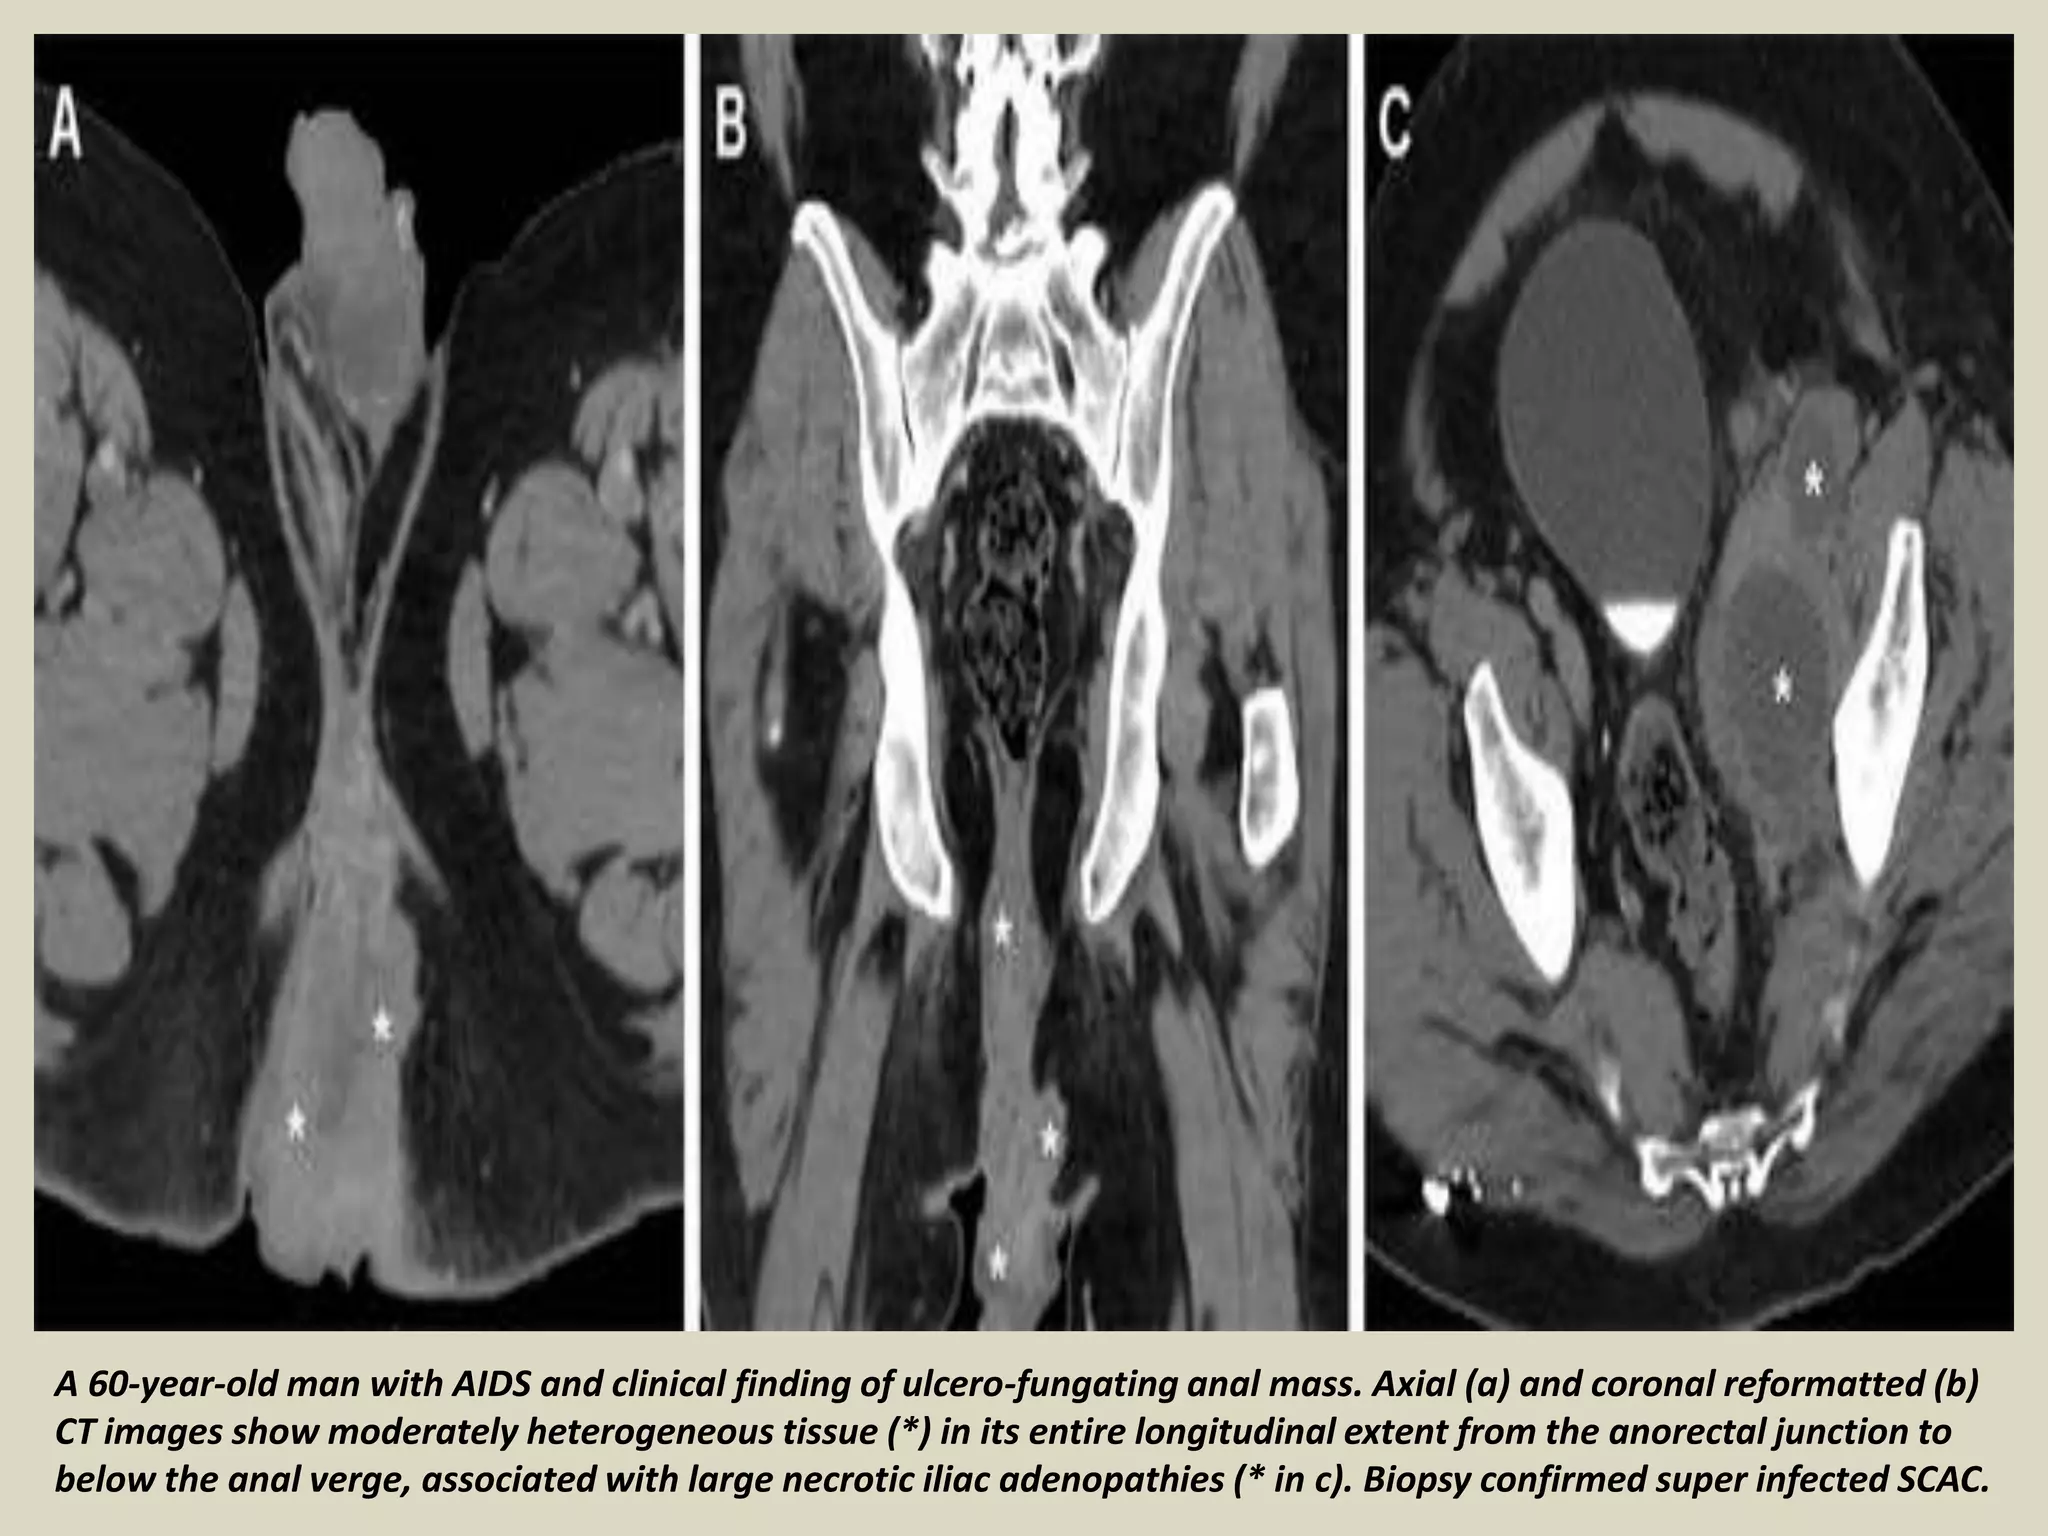

Presentation Radiological Imaging Of Anal Carcinoma Pptx 129752